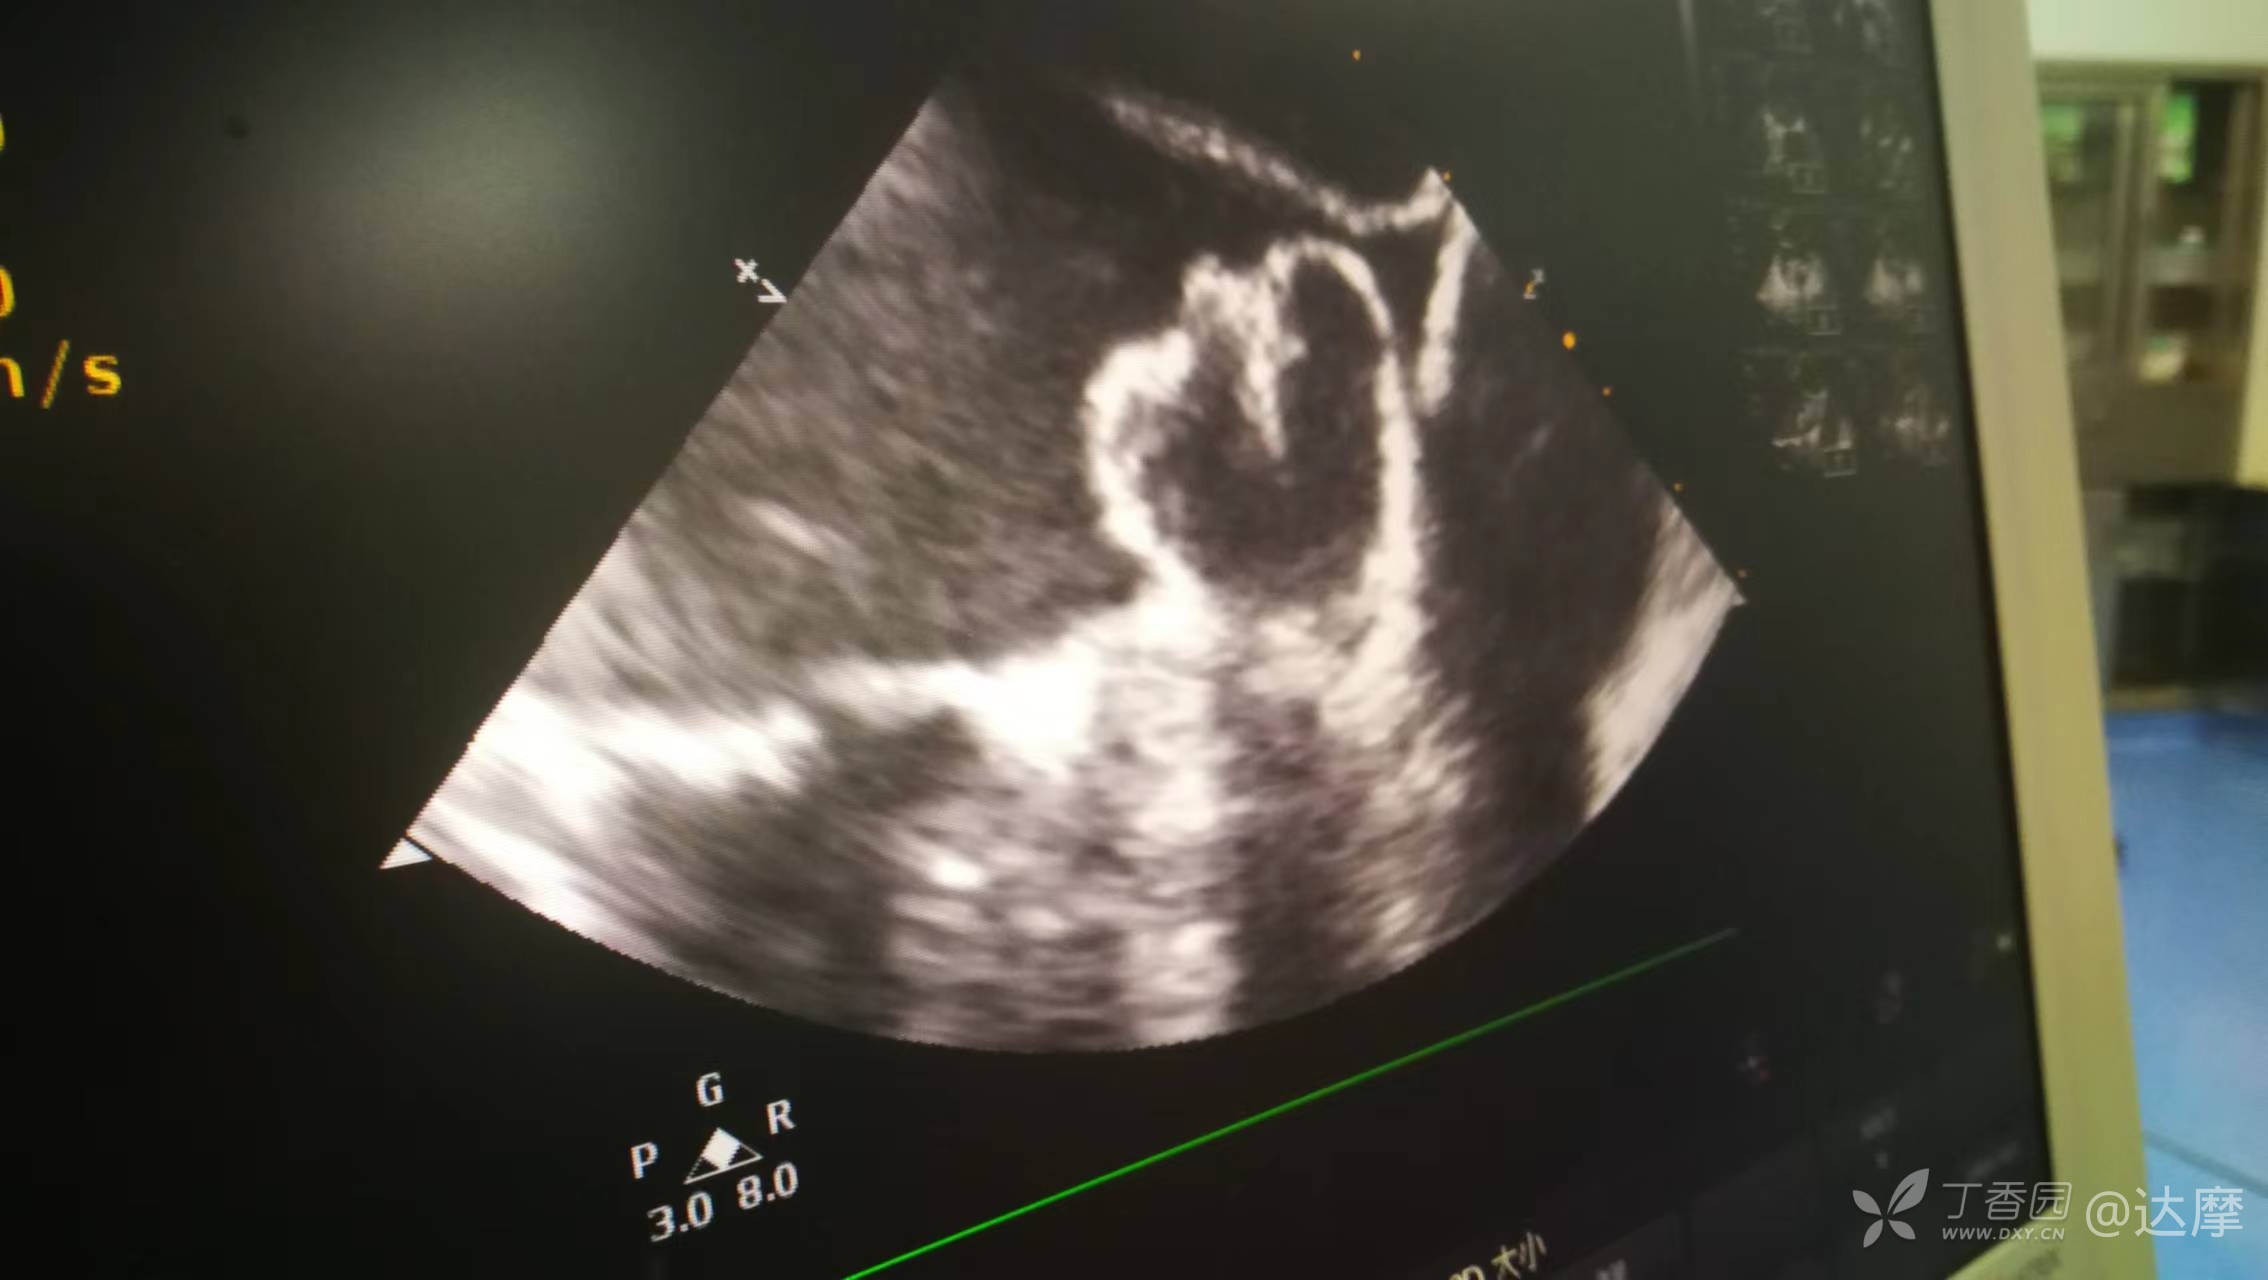

选择了当前最大的封堵器,术中尝试封堵情况如下: